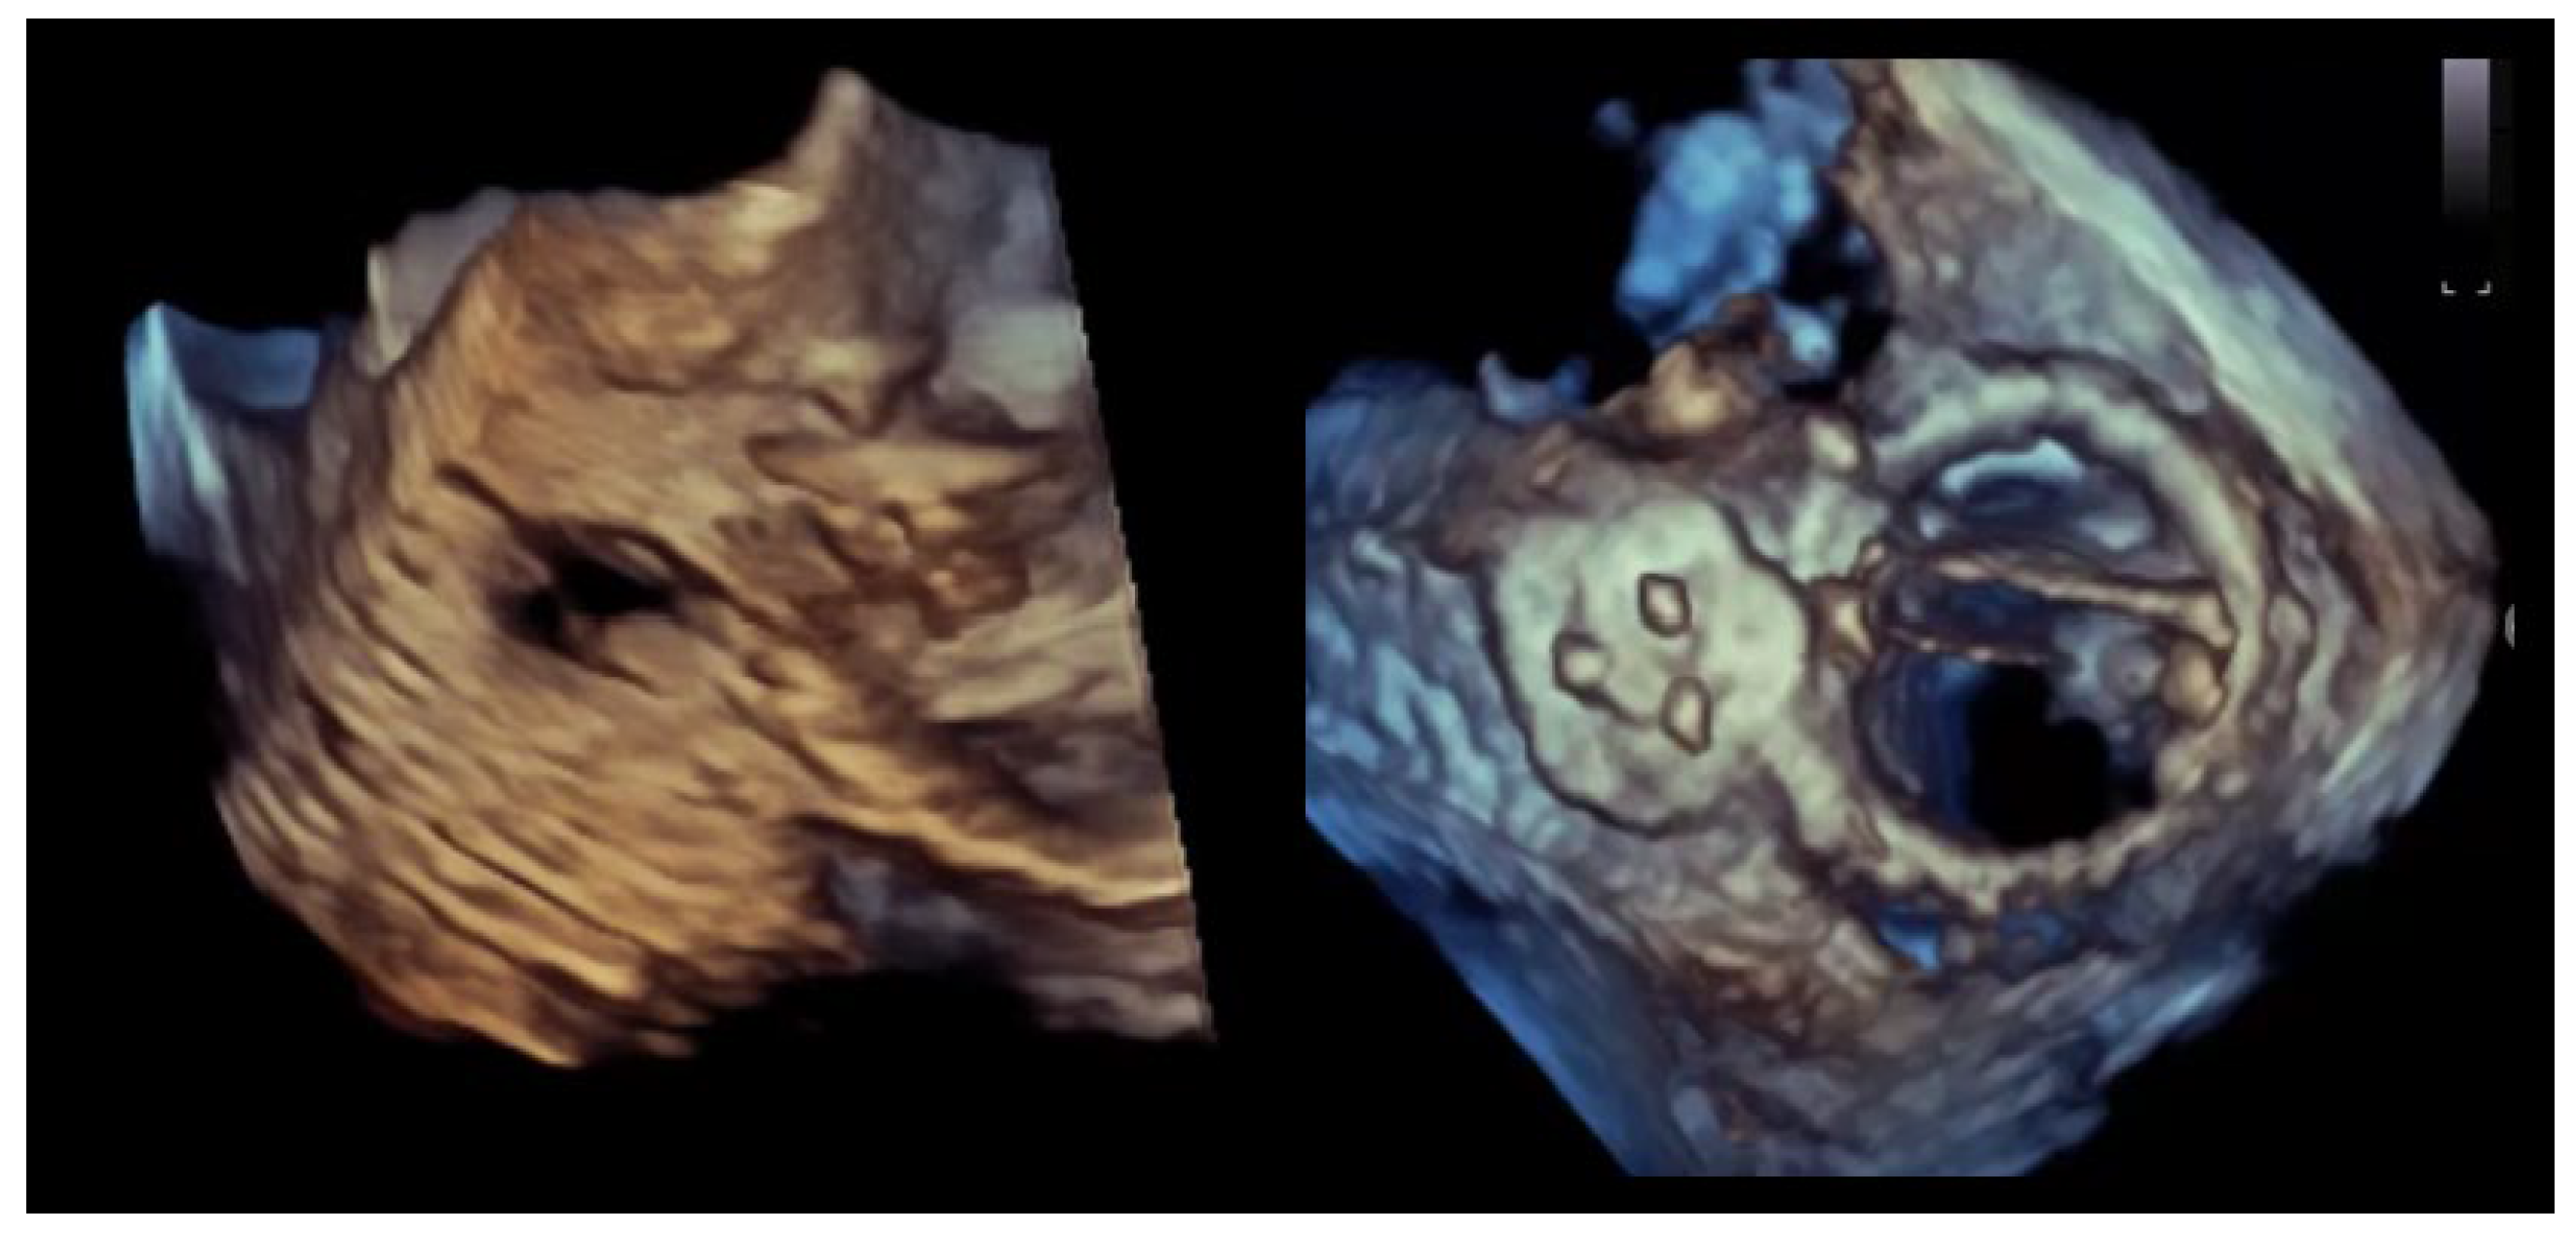

Figure 1.

Multi-orifice (two-hole) paravalvular leak demonstrated by three-dimensional transesophageal echocardiography. (Left panel): Three-dimensional transesophageal echocardiographic en-face reconstruction of the prosthetic valve illustrating the paravalvular region and surrounding annular anatomy. (Right panel): Corresponding three-dimensional color Doppler volume rendering demonstrating two spatially distinct paravalvular regurgitant orifices (arrows) along the prosthetic sewing ring. Each defect generates a separate high-velocity regurgitant jet, confirming the multi-orifice nature of the paravalvular leak rather than a single focal defect.

Figure 2.

Crescentic paravalvular leak with elongated annular involvement. (Left panel): Three-dimensional transesophageal echocardiographic reconstruction of the paravalvular region demonstrating an elongated, crescent-shaped defect extending along the prosthetic sewing ring. (Right panel): En-face three-dimensional view illustrating the continuous, non-circular geometry of the paravalvular channel, with multiple potential exit points distributed along the arc of annular dehiscence.